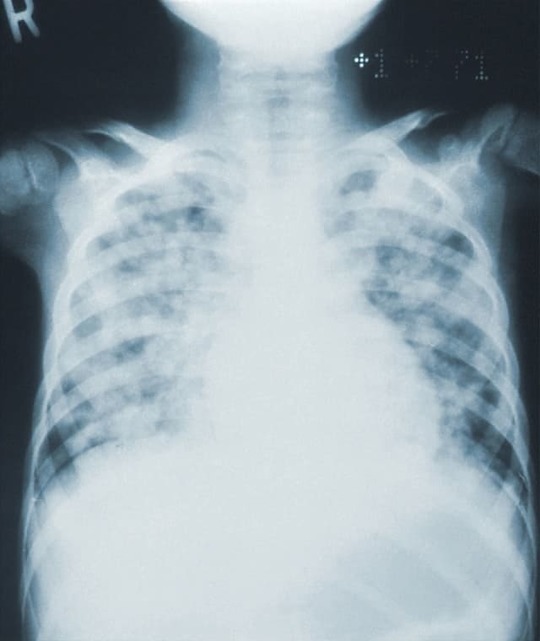

内軟骨腫の特徴は、レントゲンを撮った時骨の中心の透過性病変で石灰化があることです。単発性が多いですが、多発性の場合もあります。

調べた時、骨の腫瘍などによって骨が破壊され骨が薄く写る部分と病的な変形などが起こった部分に起きるカルシウム沈着と予想される部分が混ざっている膨隆した病変や骨が薄くなっていることがみられることなどによって判断されます。